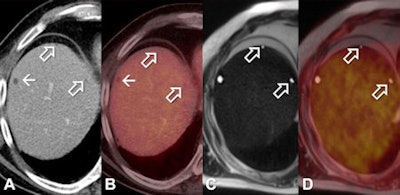

PET/MRI is more than adequate in characterizing liver lesions and provides greater lesion conspicuity than PET/CT, offering clinicians a powerful alternative for oncology imaging, according to a German study published in the November issue of the European Journal of Radiology.

PET/MRI provided better diagnostic confidence due to soft-tissue contrast and complementary information from different MRI sequences, according to lead author Dr. Karsten Beiderwellen and colleagues from University Hospital Essen, University of Duisburg-Essen, and University of Dusseldorf (EJR, Vol. 82:11, pp. e669-e675).

"The inherent soft-tissue contrast coupled with the higher spatial resolution of MRI is the main advantage over PET/CT, providing the overall higher conspicuity of liver lesions," Beiderwellen wrote in an email to AuntMinnie.com. "Plus, diffusion-weighted [MRI] helps in delineating even small lesions and offers complementary information to PET."

By comparison, MRI offers enhanced soft-tissue contrast and has proved particularly beneficial for patients with small liver lesions. The modality has shown superior results compared to CT and PET/CT for depicting and characterizing liver tumors, Beiderwellen and colleagues wrote.

The authors pointed out two key conclusions from the study. First, because integrated whole-body PET/MRI offers higher lesion conspicuity than PET/CT, more lesions can be delineated in PET/MRI.

"Second, PET/MRI offers higher diagnostic confidence in the characterization of liver lesions," they wrote. "Due to the excellent soft-tissue contrast and complementary information from different MRI sequences a correct differentiation especially of small liver lesions is possible."